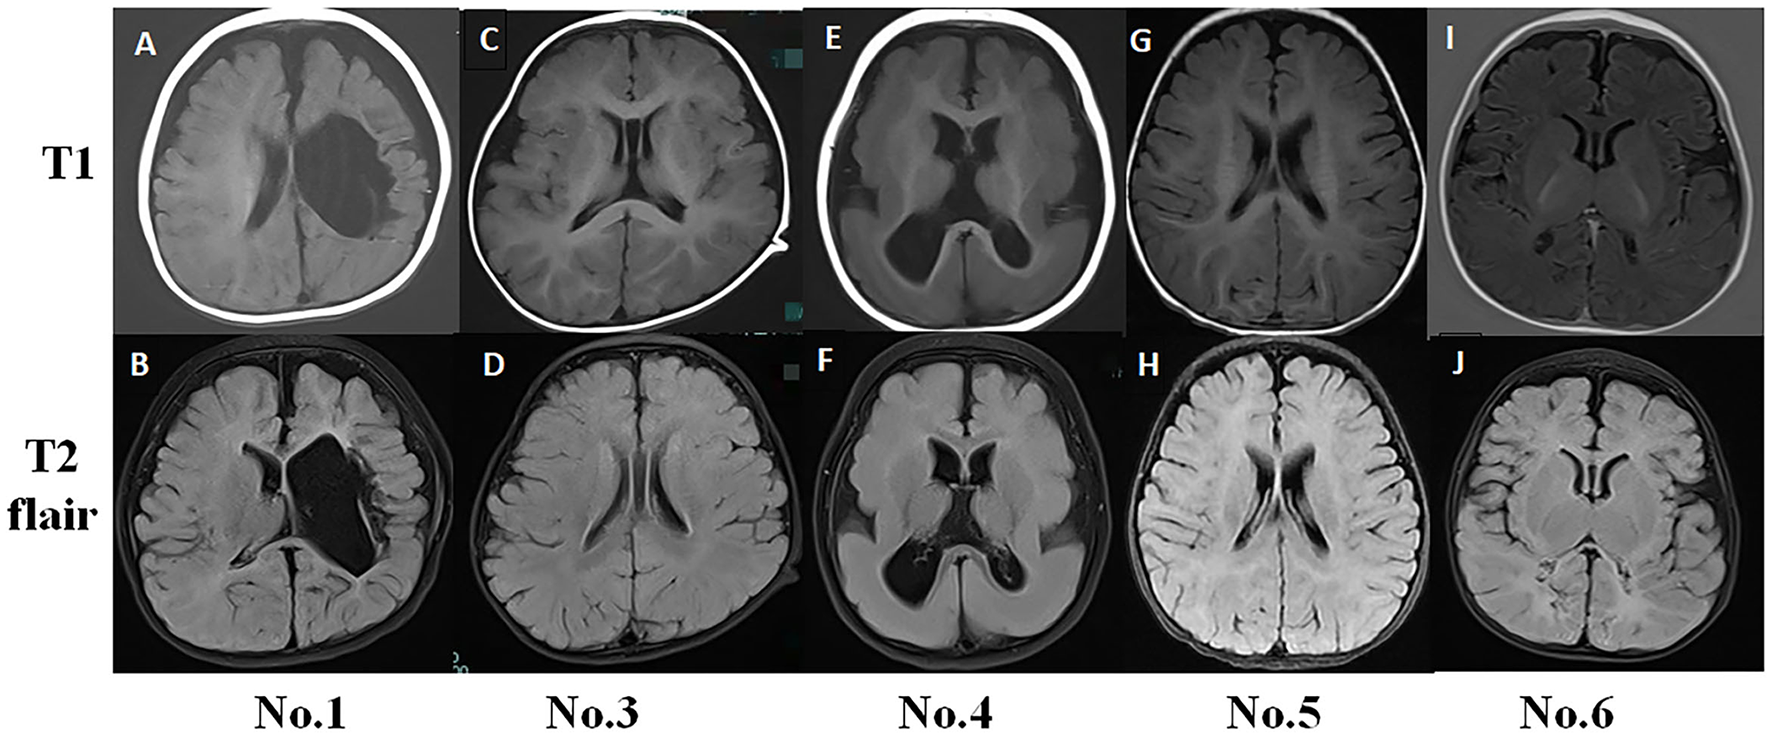

Figure 1

Typical magnetic resonance imaging (MRI) findings in infantile spasm (IS) patients. (A,B) No. 1 MRI (8-month-old) showed left hemisphere softening, left ventricle deformity, and cerebral peduncle atrophy. (C,D) No. 3 MRI (15-month-old) had normal findings. (E,F) No. 4 MRI (11-month-old) showed pachygyria. (G,H) No. 5 MRI (6-month-old) had normal findings. (I,J) No. 6 MRI (4-month-old) exhibited abnormal signals in the bilateral occipital and parietal lobes.

Typical MRI Examinations

No. 1 MRI T1 and T2 flair examination showed left hemisphere softening, left ventricle deformity, and cerebral peduncle atrophy. The MRI findings for No. 3 and No. 5 were normal. No. 4 MRI showed pachygyria (Figure 1).

The fast-wave overconnectivity and the slow-wave high local connectivity and defense capabilities may reflect IS pathogenesis, and the alpha band played the most important role during the waking periods, especially in the frontal lobes. Up to 30% of patients with focal epilepsy have seizures originating from the frontal lobe, accounting for the most common extratemporal type (26). We observed that EEG functional network changed when spasms occurred, especially in the forehead, which was different from the brain lesion location on MRI (Figure 1). Researchers have provided important insight into the pathophysiology of ES by performing invasive recording studies that have shown that ES originates locally in the cortex and has been characterized by rapid propagation to the premotor and motor cortices (27). Given the young age of the studied cases, thin skulls are not suitable for invasive recording, but maybe the above research can explain our findings on the characteristics of ictal onset. However, the reason for the active functional network in IS patients' forehead requires further research.